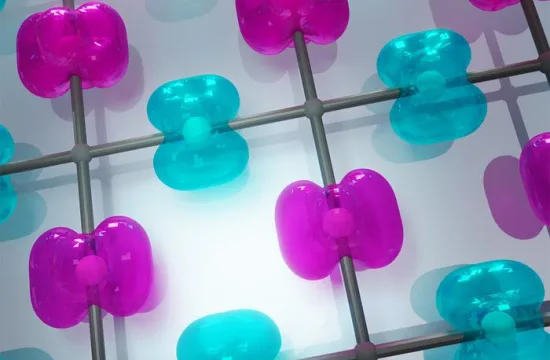

- A still from an animation that shows the steps of how blood stem cells take root in the body of a zebrafish to generate blood. (Credit: Boston Children’s Hospital/Stem Cell Research Program)

The steps are detailed in an animation narrated by senior investigator Leonard Zon, director of the Stem Cell Research Program and professor of stem cell and regenerative biology at Harvard Medical School.

“The same process occurs during a bone-marrow transplant as occurs in the body naturally,” says Zon. “Our direct visualization gives us a series of steps to target, and in theory we can look for drugs that affect every step of that process.”

“Stem cell and bone marrow transplants are still very much a black box — cells are introduced into a patient and later on we can measure recovery of their blood system, but what happens in between can’t be seen,” says Owen Tamplin, the paper’s co-first author. “Now we have a system where we can actually watch that middle step. “